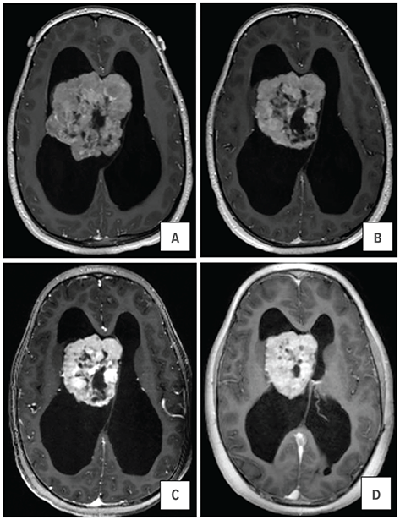

The paper describes treatment outcomes involving a 7-year-old patient who developed an exceptionally large SEGA. The tumor’s deep location in the brain made surgical resection a poor option.

Franz recommended starting everolimus. In 2.5 months, the tumor shrank from 209 cm3 to 58 cm3, a 72 percent reduction. Everolimus therapy continued, shrinking the tumor further. Surgical resection was not needed.